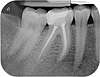

Necrose dentaire

radiographie dentaire